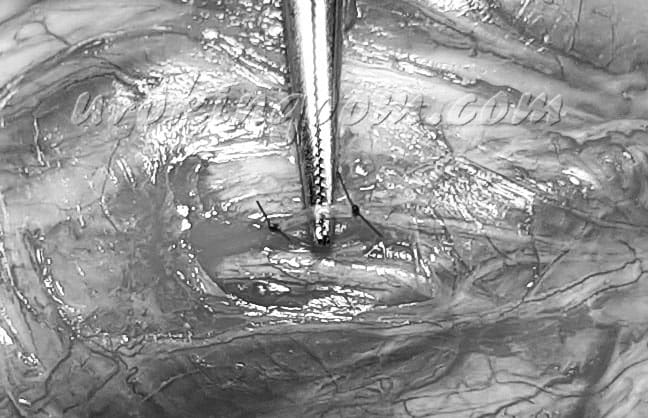

源於醫學文獻報告的選擇性背神經阻斷手術並加以改良,微創選擇性背神經阻斷手術是應用精細的顯微手術技巧阻斷部分背神經分支,以治療因陰莖過度敏感而導致的早洩,在局部麻醉下進行。手術時採平躺姿勢,於陰莖深部及周圍使用創新的雙重局部麻醉方法,延長有效麻醉時間。手術時在龜頭冠狀溝下方選擇適當位置將包皮切出一道環狀傷口並將包皮褪下,小心游離傷口內面筋膜組織,需保留鄰近血管及正常組織。在陰莖兩側選擇部分的背神經分支,仔細小心分離且避免傷害鄰近組織,以細線綁紮並截斷分離出的背神經分支,阻斷部分神經傳導,降低神經的敏感度以延遲射精時間(圖二)。最後使用可吸收微細縫線縫合傷口,完成手術。